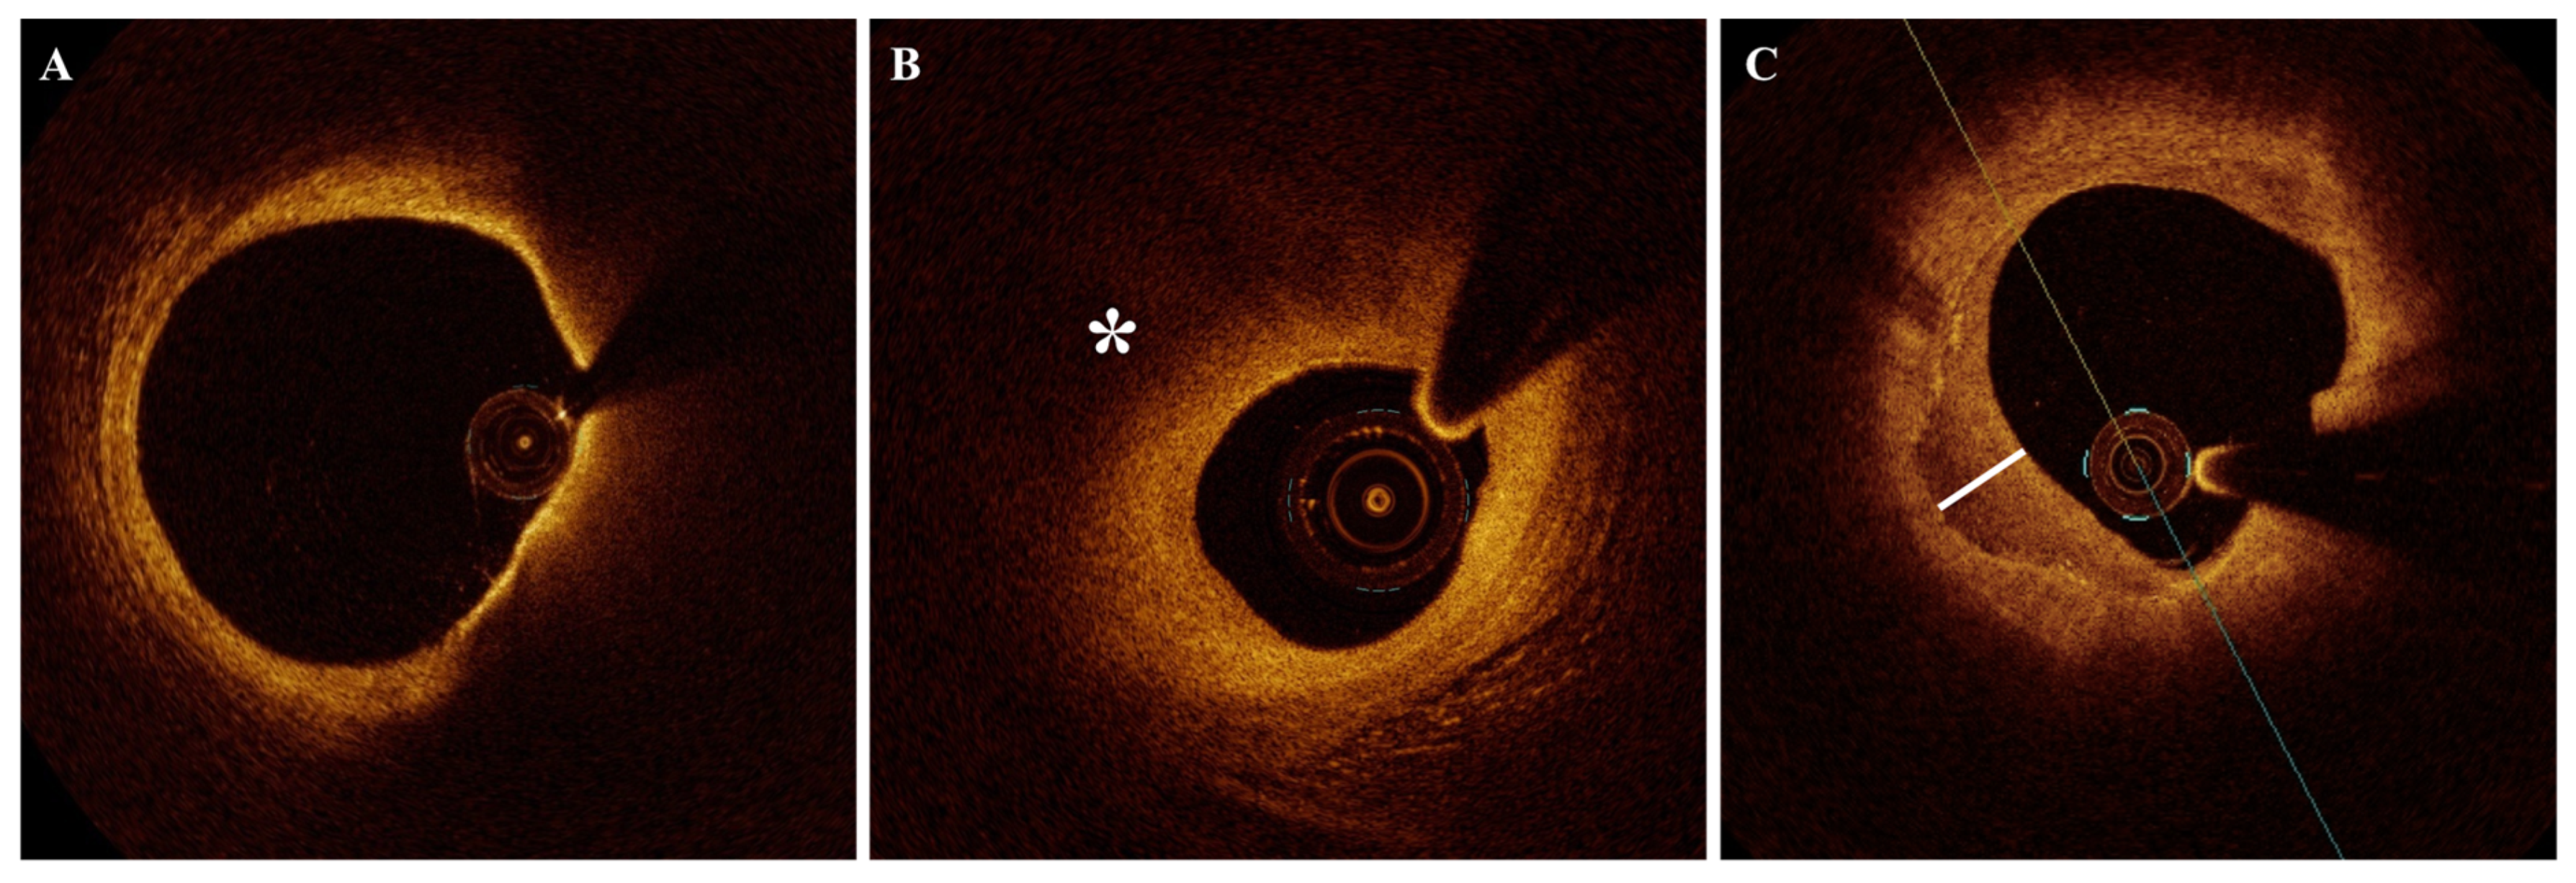

2.5. Cholesterol Crystals (CCs)

2.7. Calcifications

2.8. Previous Ruptures (Cavities Within the Plaque in Stable Patients)